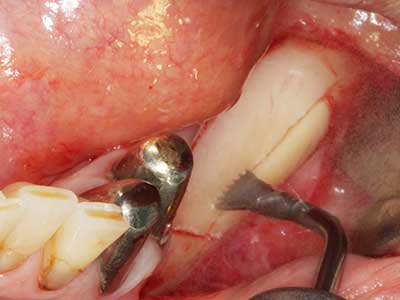

Indication: Preparation near nerves

As noted above, indications for piezo surgery can also be found in the field of conservative dental surgery. Special working tips simplify the exposure of root tips and make it easier to protect nerves and sinus mucous membranes, particularly in the lower premolar and upper posterior tooth regions. Angled diamond tips are used to precisely prepare the resection cavity for the retrograde root filler material for unsealed apical obturation. The ultrasonic technology means the tips can be very slender, which improves the view and the size of the access cavity. As a result, the application of ultrasonic surgery for this indication is one of the standard procedures for apical resection (Del Fabbro, Tsesis et al. 2010, Scarano, Artese et al. 2012).

Indication: Apical resection

When surgical procedures are performed on bone in the immediate vicinity of sensitive structures such as blood vessels or nerves, rotary instruments pose a significant risk of iatrogenic injury. Piezoelectric devices can be helpful for preparation of bone covers and removal of hard tissue close to nerves, particularly for exposure of nerves after iatrogenic injury but also during nerve lateralization for resective and reconstructive procedures or implant placement (Fig. 17-20). Light contact between the piezotip and the nerve does not generally result in damage but proceeding incautiously with saw-like motions or attachments where a residual bone substrate remains may cause temporary or even permanent nerve damage. However, the risk of damage is considered to be substantially lower than when using saws or milling instruments (Pereira, Gealh et al. 2014).